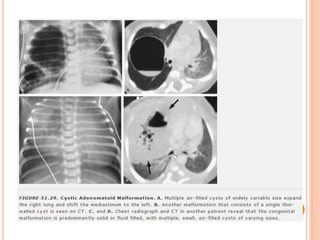

 Cistos pulmonares congênitos: paredes finas, mais

em lobos inferiores, assintomáticos.

 Malformação adenomatóide cística: lesão

congênita, tecido pulmonar anormal, com tecido

adenomatoso displásico

 Primeiros dias de vida: contém líquido, aparência

sólida

 Ar substitui líquido: cistos radiotransparentes

 Diagnóstico diferencial com hérnia diafragmática

congênita